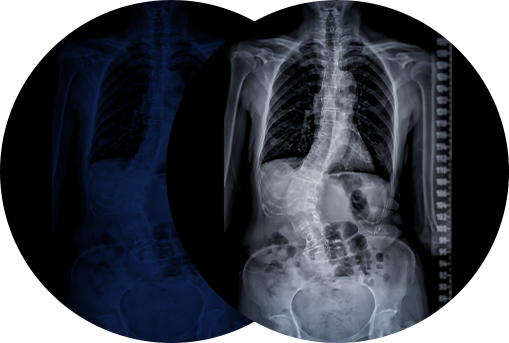

척추측만증 · 도수치료

척추측만증은 정면에서 봤을 때 척추가 I모양으로 곧게 펴져 있어야 하는데, S자로 휘어있는 상태를 말합니다.

전체 소아청소년기 인구의 약 1.5~3% 정도에서 척추측만증이 발생하는데, 성장기 시기 척추가 발달하면서 증상이 심해지는 경우가 많으며 성장이 다 끝난 후에 호전되기는 힘들기 때문에 늦기 전 비수술적인 방법의 도수치료 등을 받는 것이 필요합니다.